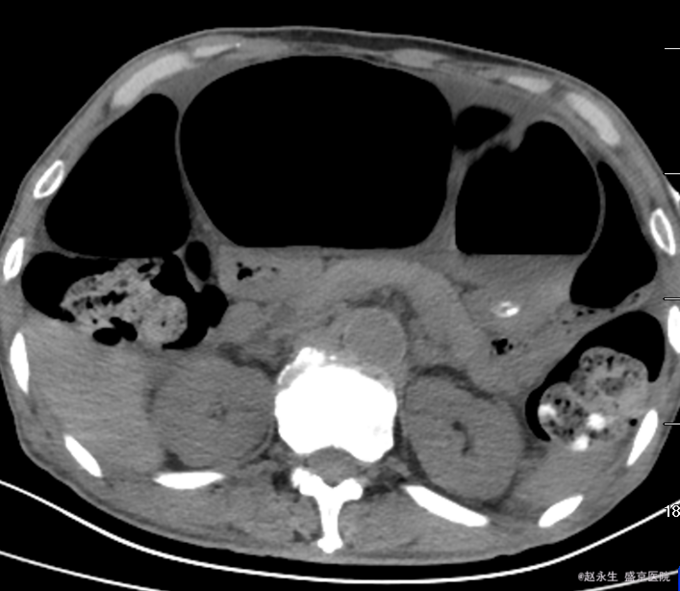

查体::腹膨隆,未见肠型及蠕动波,未触及明确包块,全腹压痛,反跳痛及肌紧张,肝区叩痛阴性,肾区叩痛阴性,Murphy征阴性。肝浊音界未见减少,移动性浊音阳性,未闻及肠鸣音。 辅助检查:急诊查腹部CT平扫提示:乙状结肠扭转,肠梗阻.盆腔多发渗出,积液.

诊断:乙状结肠扭转 治疗:急诊全麻下行剖腹探查,乙状结肠部分切除,远端闭锁,近端造瘘术。术中探查见左侧腹腔巨大肠畔,张力较高,肠壁因扩张导致菲薄,肠壁暗红有点状缺血坏死征象,有一处肠壁浆膜裂开,有少许出血,扩张肠管周围及盆腹腔有草黄色渗出,吸净渗出,轻轻将扩张肠管娩出腹壁外,证实扩张的肠管为乙状结肠,仔细检查,见乙状结肠系膜较长,肠管顺时针扭转360°形成完全性肠梗阻,横结肠,降结肠扩张,有较多内容物,未触及肿瘤,胃空虚。